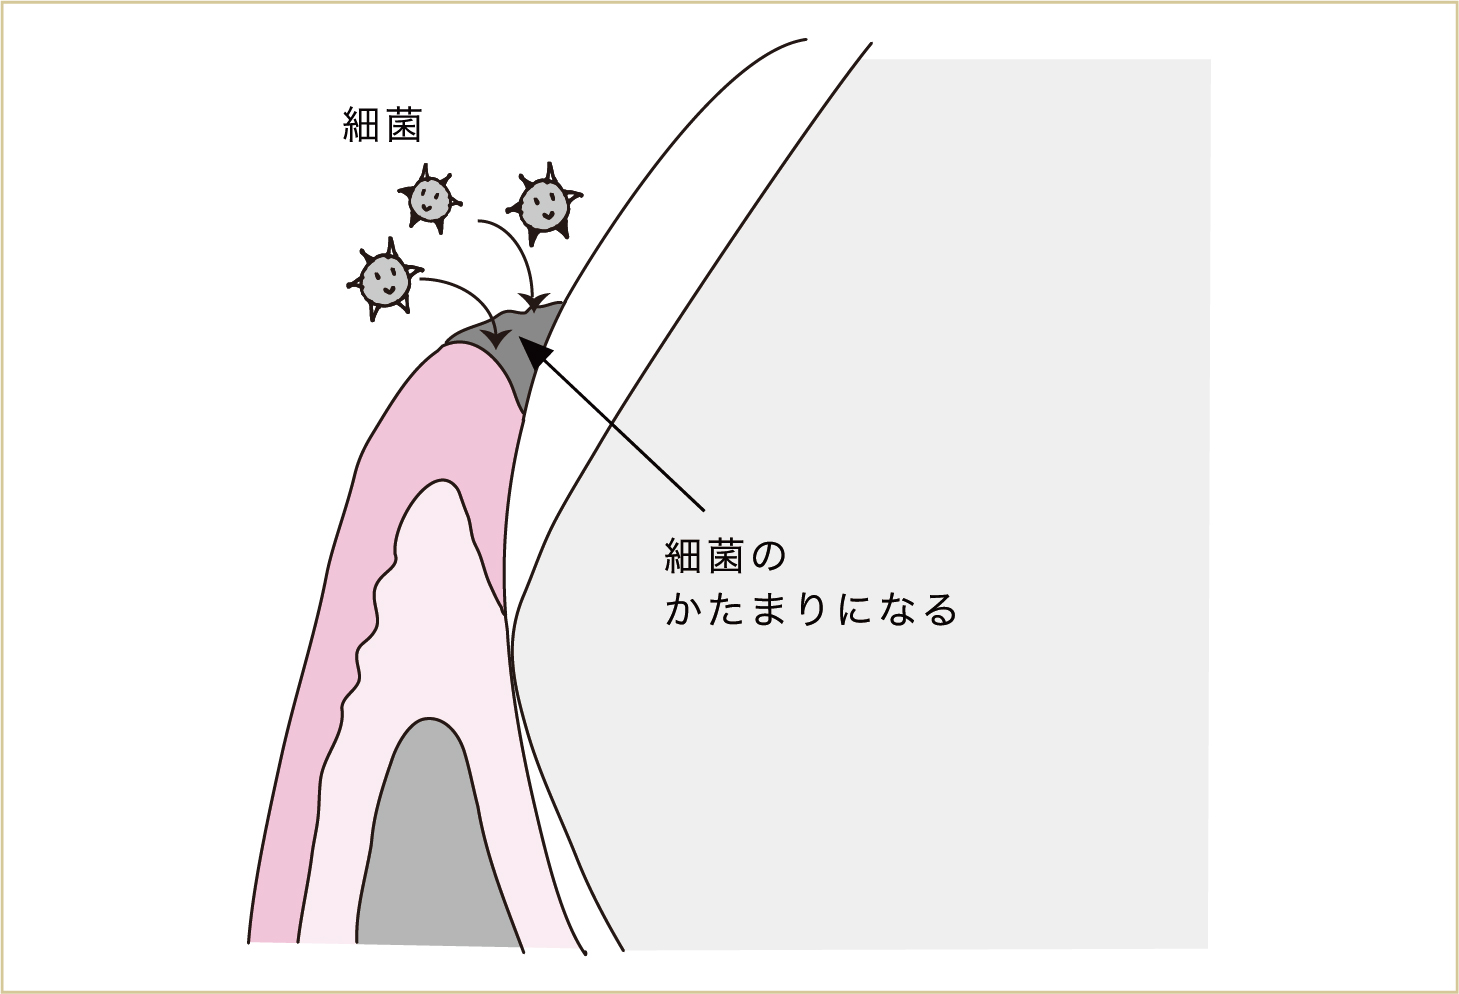

このみがき残しの中に、唾液中の細菌が入ってきます(唾液の中には雨粒一滴ぐらいの中に10億という数の細菌がいるのが普通)。つまり、このみがき残しの部分は細菌のかたまりになっていくわけです。

みがき残しの中に唾液中の細菌が入り込む。